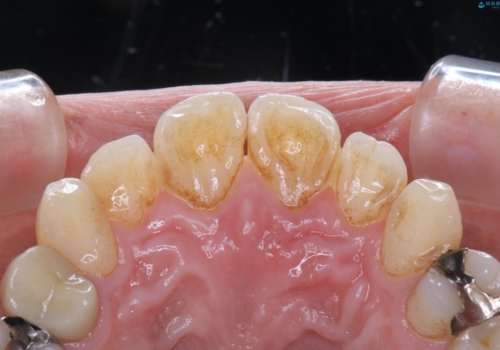

- 歯のホワイトニングを希望されて来院された患者様です。

レーザーを用いたホワイトニングを行いました。

施術前後の変化に大変満足されていました。

薬剤を塗布し、レーザー照射を3セット行いました。

オフィスホワイトニングは、高濃度の過酸化水素を使ったホワイトニング剤を扱うことができるので、1回の施術で白さを大きくアップすることが可能です。また、後戻りはおよそ半年から1年程度です。白さを強化、持続させるためにオフィスホワイトニング後にホームホワイトニングを行うこと(デュアルホワイトニング)をおすすめしました。